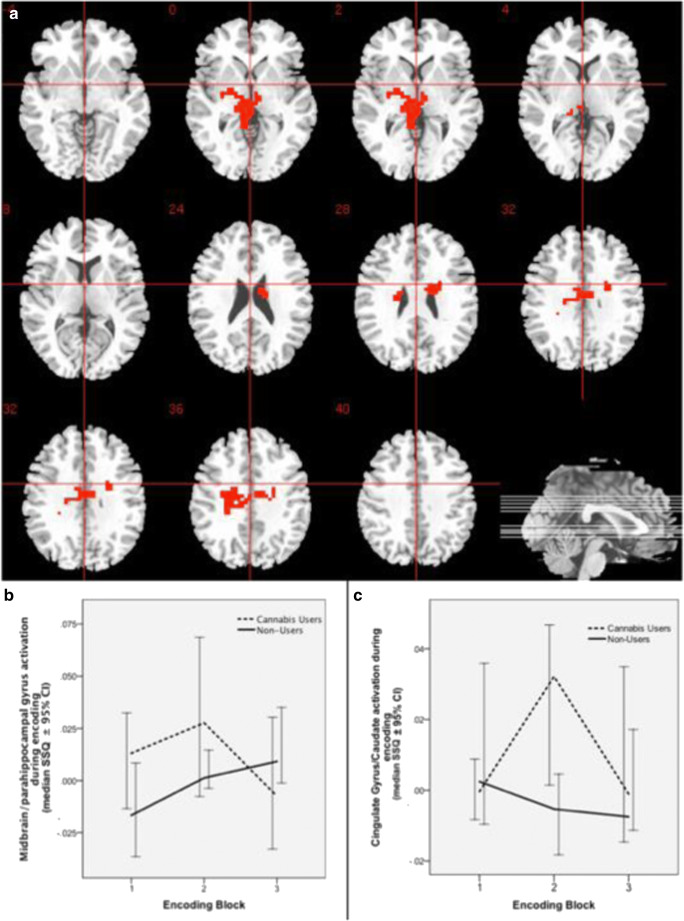

Group comparison (CU vs NU) of change in brain activation during learning over repeated encoding blocks

There was a significant interaction between group (CU vs NU) and learning over repeated encoding blocks in a network of brain areas that included the midbrain bilaterally extending to the parahippocampal gyrus on the left and the thalamus bilaterally (p = 0.00939, partial eta-squared =0.180); left cingulate gyrus and caudate extending to the insula (p = 0.00939, partial eta-squared = 0.100) (Table 2, Fig. 2). In the midbrain cluster extending to the parahippocampal gyrus and thalamus, there was a pattern of progressive increase in brain activation with repeated presentation of encoding blocks in NU, which was disrupted in CU. In the cingulate gyrus as well as in the body of the caudate, there was a pattern of progressive decline in activation over repeated encoding blocks in NU, while in CU there was an increase in activation from block 1 to block 2 followed by a decline over successive trials. Post hoc power analysis using effect-size estimate (partial eta-squared = 0.180; effect-size f = 0.468) from the midbrain/parahippocampal gyrus cluster found that our sample (total N = 42) had 84.2% power (alpha = 0.05, 2-tailed; G-POWER (Faul et al. ref. 2007)) to detect differences in hippocampal activation between the CU and NU groups.

Direct comparison of the association between change in brain activation over repeated encoding blocks and incremental novel learning (as indexed by the ‘new learning score’) over the same encoding blocks confirmed the learning-related differential pattern of activation in the two groups. CU showed significantly greater correlation than NU between repetition-related change in activation during encoding and the number of successfully learned new word-pairs over the same successive encoding blocks in the midbrain bilaterally, extending to the left parahippocampal gyrus, culmen and thalamus. NU showed significantly greater correlation than CU in the left cingulate gyrus, extending to the ipsilateral postcentral gyrus, inferior parietal lobule and tail of caudate (Table 2, Online Resource 6).

The main focus of this study was to investigate the neurophysiological abnormalities that may underlie impairments in verbal learning and memory in regular cannabis users. Using a paired associate verbal learning task in conjunction with fMRI and an analytic approach that allowed us to investigate progressive changes in learning-related engagement of different brain regions, we show that CU had a slower learning trajectory and employed a significantly different pattern of recruitment of brain regions relative to NU while learning word-pairs. The verbal learning task employed had a relatively modest level of difficulty, such that performances in both the CU and NU groups reached ceiling and were not significantly different as indexed by their total recall score. Nevertheless, the gradient of learning across the repeated trials was significantly different between NU and CU. NU seemed to learn the word-pairs faster than CU, such that performance in NU improved significantly from recall block 1 to reach near the ceiling by recall block 2, with no significant further improvement as indicated by lack of significant difference in recall scores between blocks 2 and 3 and between blocks 3 and 4. In contrast, CU seemed to continue to learn with progressive improvement in recall score over successive trials until block 4, reaching a similar performance level as NU only by recall block 3. While learning the verbal stimuli over repeated encoding blocks, NU showed a progressive increase in recruitment of a cluster of brain regions that included the midbrain, parahippocampal gyrus and thalamus, which paralleled the progressive improvement in total number of words learnt per block as indexed by subsequent recall. However, this pattern of progressive increase in recruitment of these brain regions was disrupted in CU, who engaged these regions to a greater extent than NU to start with. Furthermore, this was associated with the recruitment of additional regions. Progressive change in midbrain/parahippocampal function over successive encoding blocks showed a stronger correlation with new word-pairs learnt over the same blocks in CU than in NU suggesting that slower verbal learning in CU was a consequence of disrupted parahippocampal and midbrain function. CU seemed to compensate for this by engaging the cingulate cortex and caudate to a greater extent than in NU during encoding to attain the same level of subsequent recall performance.